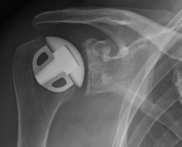

Abbildung9Abbildung10 Special prostheses such as an inverse shoulder prosthesis (syn.: "Delta prosthesis", "Grammont prosthesis") for the combination of severe omarthrosis with joint instability and rotator cuff defects

Right: radiograph of an inverse shoulder prosthesis for rotator cuff defect arthropathy.

left: Inverted shoulder prosthesis (Aequalis reversed type, Tornier company).